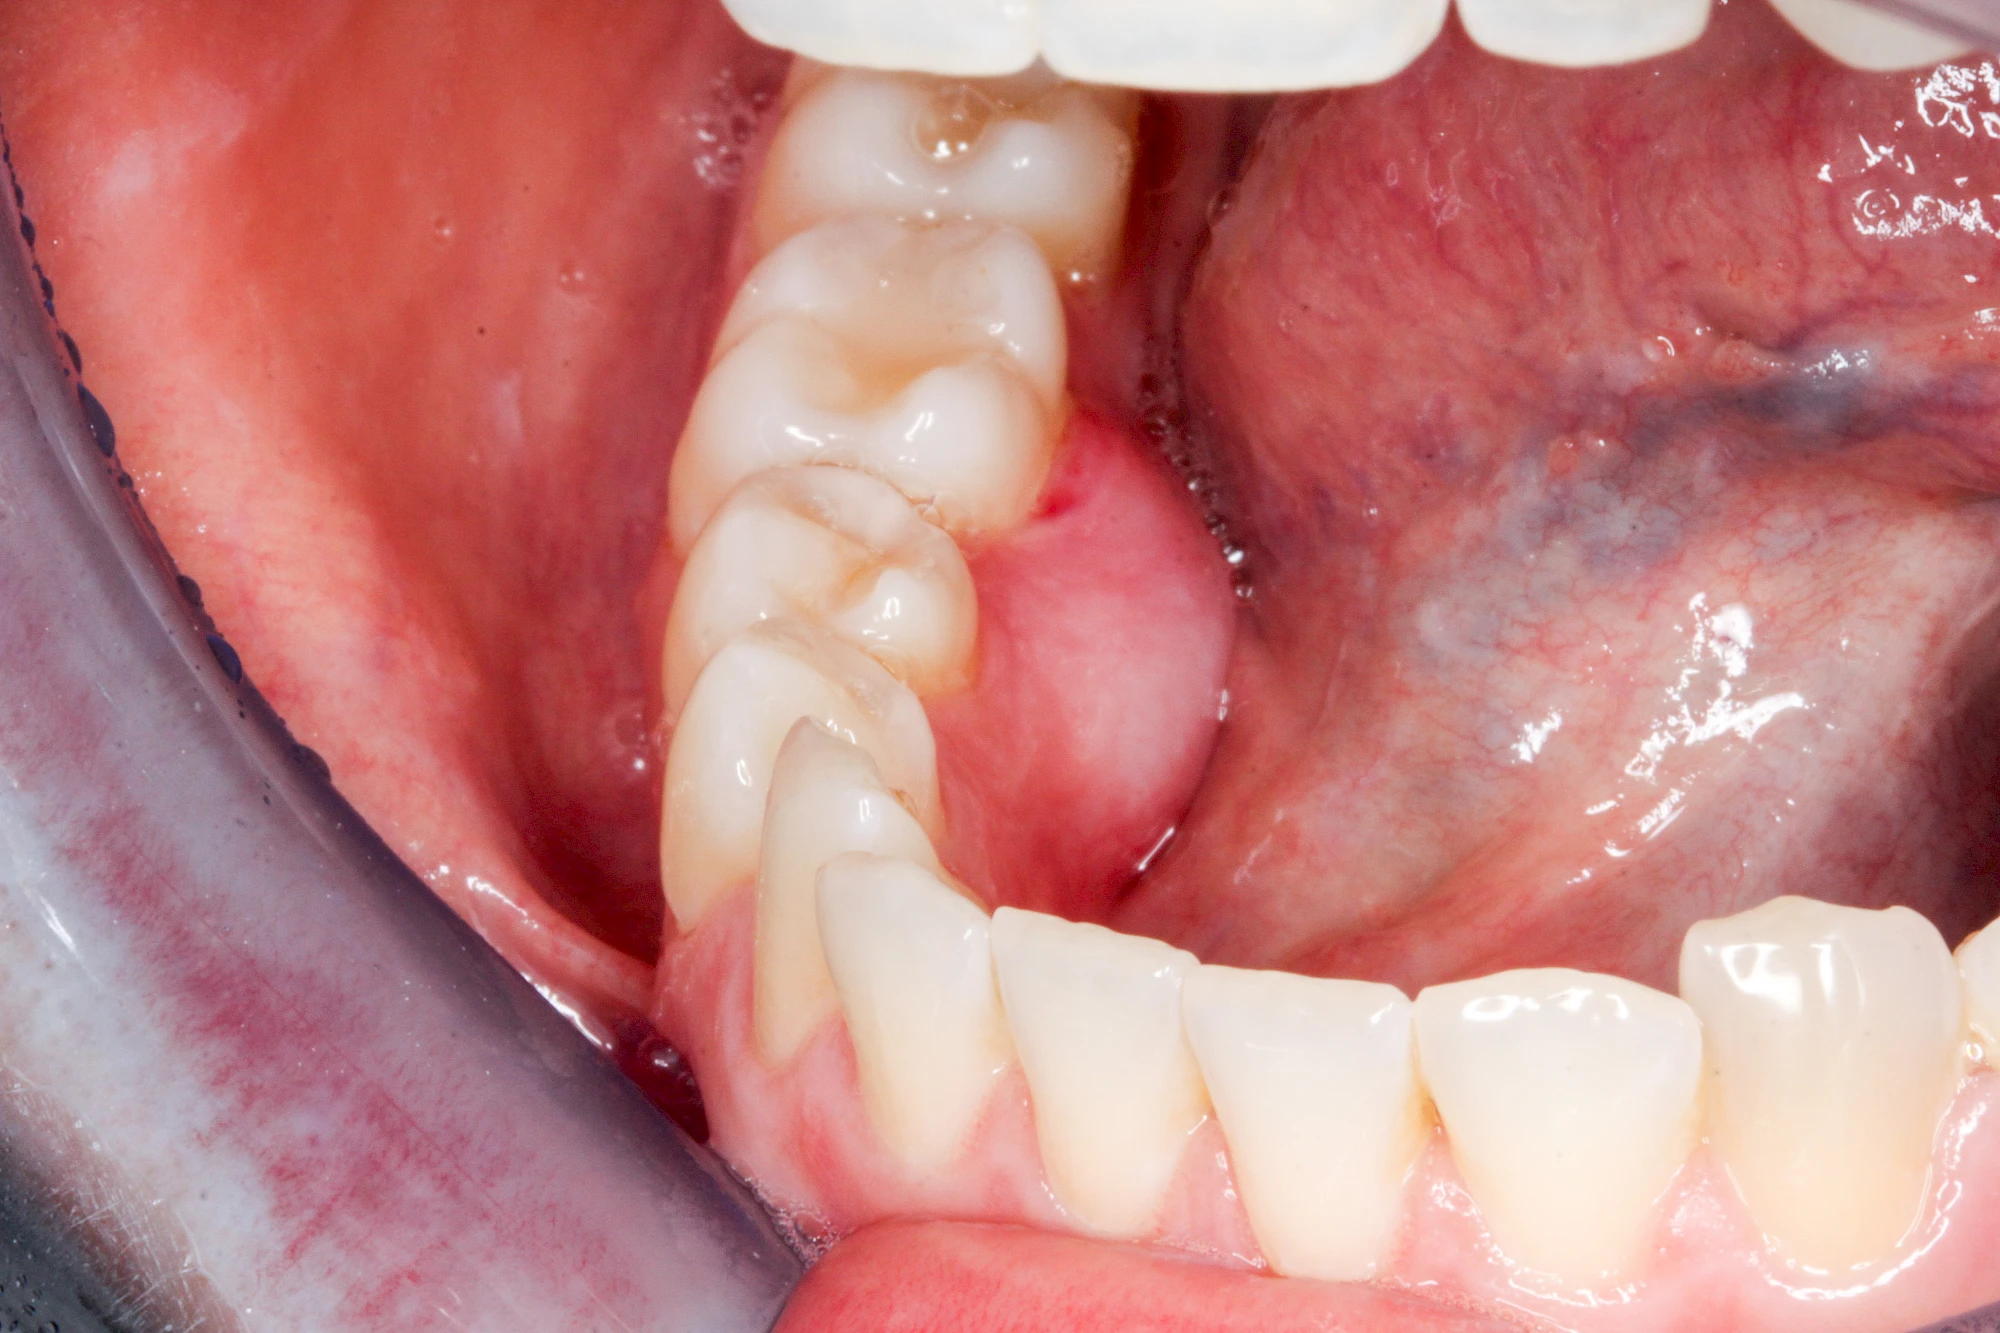

Im Laufe der menschlichen Entwicklung haben sich die Kiefer aufgrund unserer Nahrungsumstellung rückgebildet. Die Weisheitszähne haben daher oft keinen Platz mehr. Bei ca. 30 % der Menschen sind diese Zähne schon gar nicht mehr angelegt. Zum Teil liegen die Zähne versteckt (retiniert) im Kiefer und sind nicht sichtbar. Hin und wieder brechen die Zähne zwar durch die Schleimhaut, aber nicht vollständig – es handelt sich um einen erschwerten Zahndurchbruch (dentitio difficilis). Dann sind die Zähne noch teilweise bedeckt von einer "Schleimhautkapuze". Gehen hier Speisereste und Bakterien unter die Schleimhautkapuze kann sich eine sogenannte Schlupfwinkelinfektion bilden. Diese Entzündungen treten spontan auf, sind häufig sehr schmerzhaft und die Mundöffnung ist eingeschränkt. Hier ist umgehend der Zahnarzt zu kontaktieren.